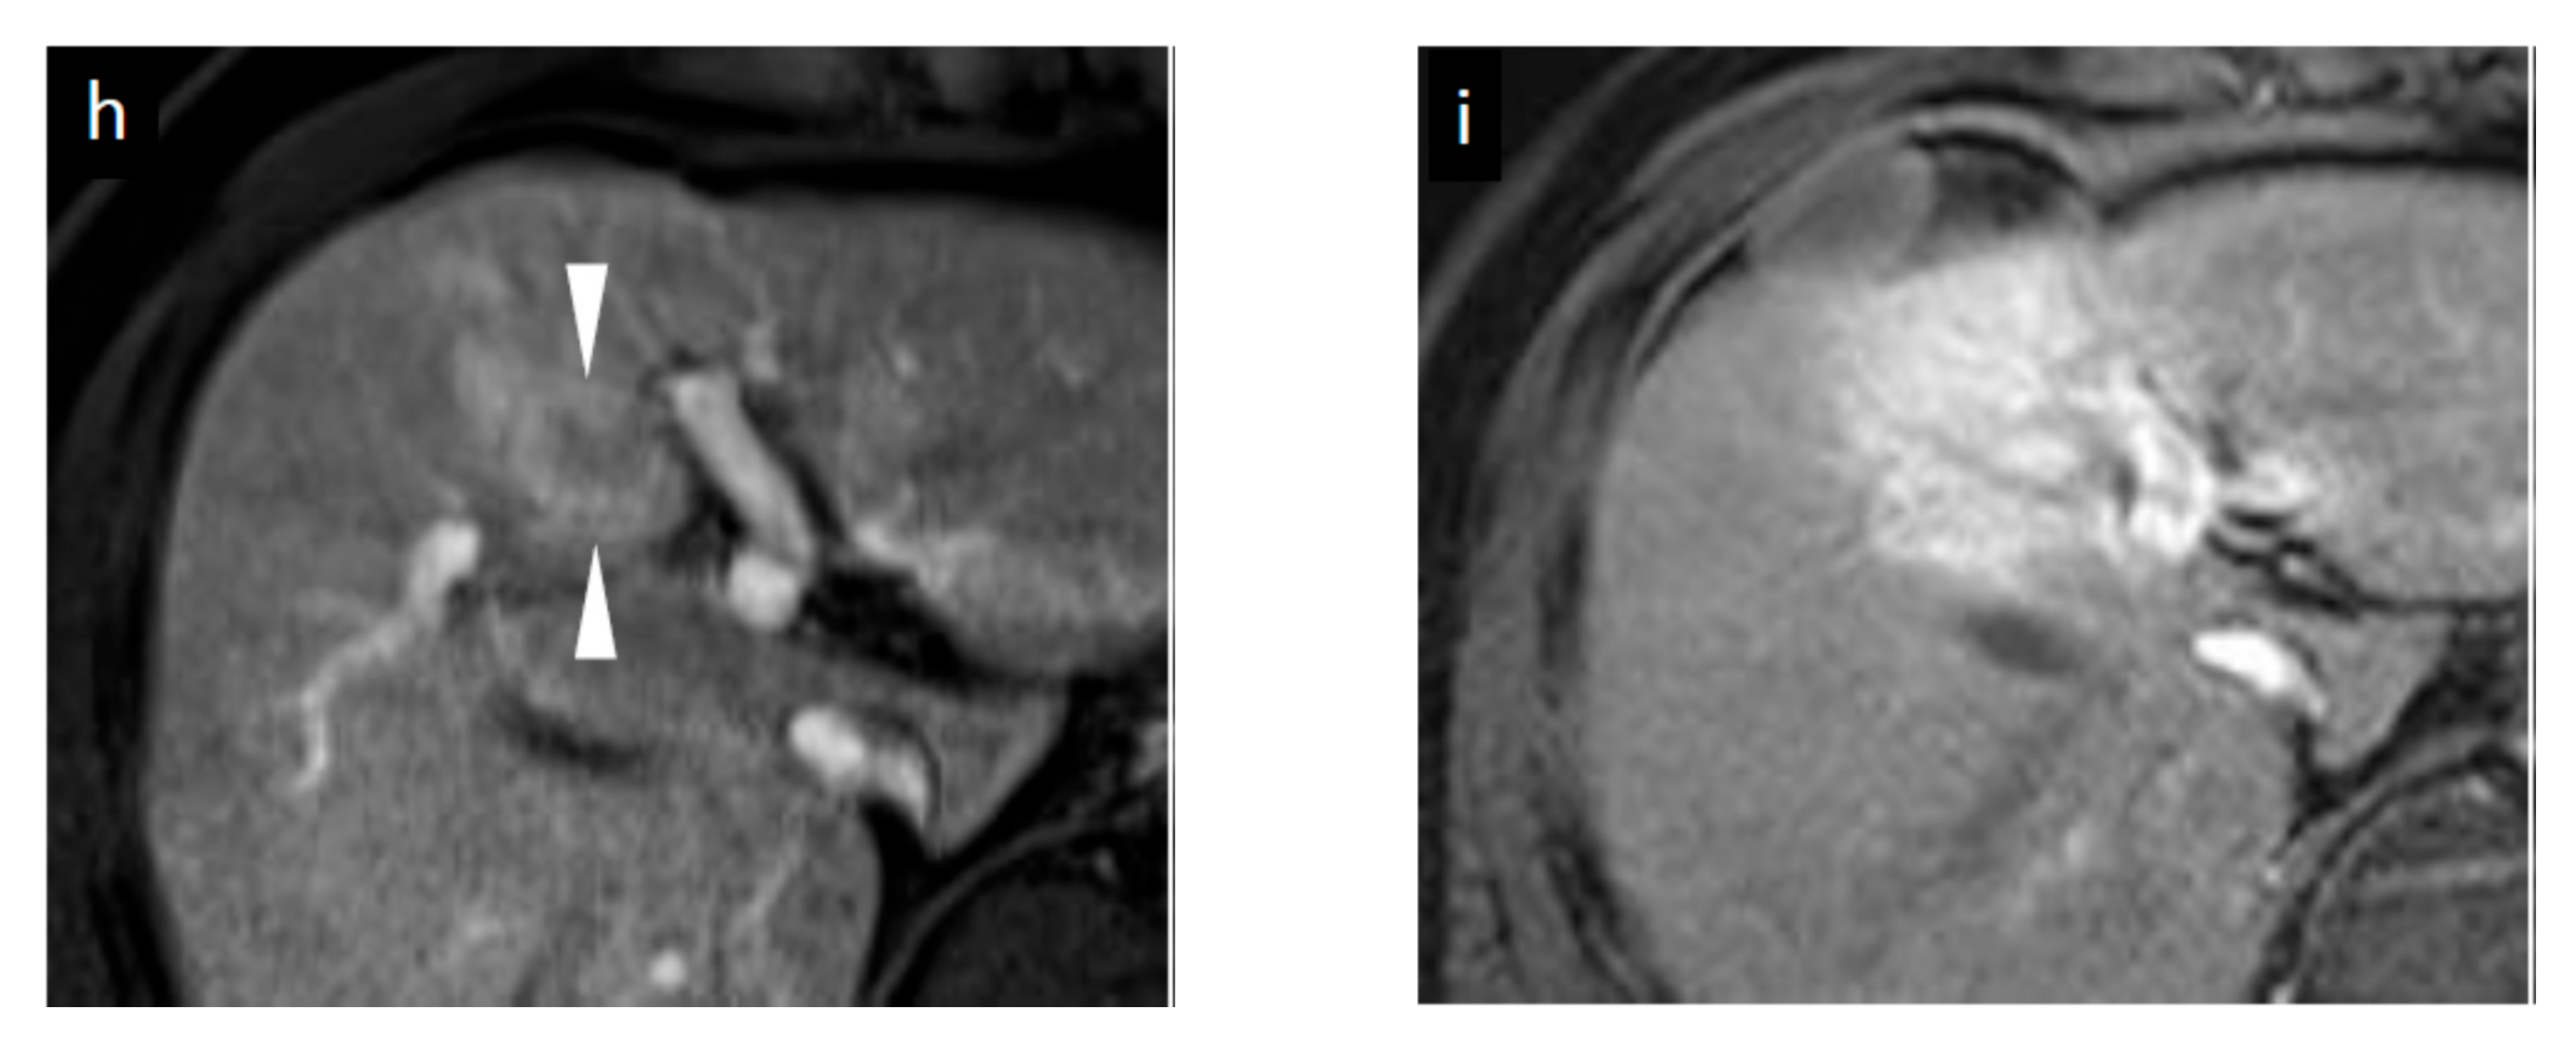

Figure 3.

Grayscale ultrasound (US) and contrast-enhanced US with Sonazoid (SCEUS) images before and after radiotherapy (RT) for an HCC lesion (maximum diameter: 34 mm) in segment III/IV, evaluated as residue after RT. RT was selected as treatment because the lesion was located adjacent to the left portal vein and the tumor size was more than 3 cm (as the maximum diameter). Hypofractionated radiotherapy was performed as the bowel organ was adjacent to the lesion. Before RT (a–c): A hyperechoic lesion was observed using grayscale US (a). This lesion showed hypervascularity during arterial phase (AP) SCEUS (b) and hypoechoic (perfusion defect) during the post-vascular phase (PVP) (c). One month after RT (d–f): The tumor size did not change on grayscale US (d). Using SCEUS, the HCC lesion showed hypervascularity with a partially hypovascular area (curved arrow) during the AP (e) and was hypoechoic during the PVP (f). The surrounding liver parenchyma showed slight hypervascularity during the AP (e) and was hypoechoic during the PVP (f). Four months after RT (g–i): The tumor size did not change on grayscale US (g). Using SCEUS, the HCC lesion showed hypervascularity with a partially hypovascular area (curved arrow) during the AP (h). The surrounding liver parenchyma showed apparent hypervascularity during the AP (h). Both the HCC lesion and the surrounding liver parenchyma appeared as a perfusion defect during the PVP (i). Thirteen months after RT (j–m): The tumor size did not change on grayscale US (j). Using SCEUS, compared with 4 months after RT, the HCC lesion showed hypervascularity during the AP (k). AP SCEUS showed slight hypervascularity of the surrounding liver parenchyma (k). Both the HCC lesion and the surrounding liver parenchyma appeared as a perfusion defect during the PVP (l). The boundary between the HCC and the surrounding liver parenchyma was unclear (l). After re-injection of Sonazoid during the PVP, both the HCC and the surrounding liver parenchyma showed hypervascularity (m). In this case, tumor size reduction and the disappearance of tumor vascularity were not observed during 13 months follow-up. Arrowheads indicate the margins of the HCC lesion. Arrows show the margins of the irradiated surrounding liver parenchyma. Pathological findings obtained from irradiated HCC area (n–p), irradiated surrounding non-tumor area (q,r), and non-irradiated non-tumor area (s,t) at 13 months after RT. For the irradiated HCC area, hematoxylin and eosin (HE) staining showed obvious cell atypia. Specifically, hypercellularity and larger, irregularly shaped nuclei can be seen. The nuclear cytoplasmic ratio is significantly higher. A few multinucleated giant cancer cells can be seen (n). Silver staining showed that reticular fibers have totally disappeared, resulting in poorly differentiated HCC (o). CD34 staining showed strong diffuse expression of CD34, suggesting increased neovascularization resulting from sinusoidal capillarization and the formation of sinusoid vascular endothelium in HCC (p). Irradiated surrounding non-tumor area showing hypervascularity during arterial phase SCEUS (* mark seen in (k)): HE staining showed neither cancer cells nor hepatocytes. Infiltration of inflammation cells (†) and severe fibrosis (‡) are noted (q). CD34 staining showed diffuse expression of CD34 in infiltration of inflammation cells (†) and severe fibrosis regions (‡) (r). Non-irradiated non-tumor area: HE staining showed normal hepatocytes with the normal nucleus shape and the nuclear cytoplasmic ratio. Thin trabeculae are clearly visualized (s). The negative expression of CD34 is seen (t).